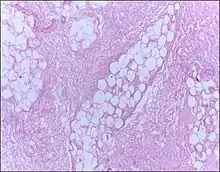

Micrograph of breast tissue showing fat necrosis. H&E stain

Fat necrosis is a form of necrosis that is caused by the action of lipases on adipocytes.[1][2]

In fat necrosis, the enzyme lipase releases fatty acids from triglycerides. The fatty acids then complex with calcium to form soaps. These soaps appear as white chalky deposits.[3]

Fat necrosis is the pattern of damage associated with the destruction of adipose tissue by trauma, hypoxia, or lipase digestion (e.g. pancreatitis). In the classic case of fat necrosis in severe acute pancreatitis, the necrosis arises because adipocytes in the peritoneum are broken and digested by inappropriately activated pancreatic enzymes. Stored triglycerides in the adipocytes are released and split by pancreatic lipases into fatty acids and glycerol molecules. The resultant fatty acids react with extracellular calcium to make calcium soaps (i.e. fatty acid salts) that give fat necrosis its characteristic chalky-white appearance. Fat necrosis is an example of dystrophic calcification because the calcification occurs at normal serum calcium levels.[11]